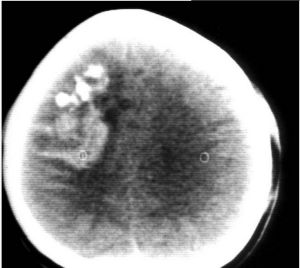

為高度惡性腫瘤,好發於2-10歲的兒童,最少者可見於幾月余小兒,大多數來源於小腦蚓部向四腦室及延髓小腦半球生長,以額、頂、顳葉區為多見。病人主要表現為神經功能障礙。常無法徹底手術切除,且復發迅速。因阻塞腦脊液循環通道,發現時多已伴有腦積水,CT及MR可發現後顱窩占位,因CT對此部位顯示不清,故推薦MR檢查。少枝膠質瘤

膠質瘤的診斷,根據其生物學特徵、年齡、性別、好發部位及臨床過程進行分析,在病史及體徵基礎上,採用電生理、超音波、放射性核素、放射學及核磁共振等輔助檢查,定位正確率幾乎是100%,定性診斷正確率可在90%以上。腦膠質瘤由於腫瘤呈浸潤性生長,與腦組織無明確分界,難以徹底切除,手術治療的原則是在保存神經功能的前提下儘可能切除腫瘤。早期腫瘤較小又位於適當部位者可爭取全部切除。位於額葉的腫瘤,可作腦葉切除。當額葉或顳葉腫瘤範圍較廣不能全部切除時,可同時切除額極或顳極作內減壓術。腫瘤位於運動、言語區而無明顯偏癱、失語者,宜注意保存神經功能,適當切除腫瘤,避免發生嚴重後遺症。腦室腫瘤宜從非功能區切開腦組織進入腦室,儘可能切除腫瘤,解除腦梗阻。位於丘腦、腦幹的膠質瘤,除小的結節性或囊性者可作切除外,一般作分流術,緩解增高的顱內壓後,進行中醫藥綜合治療。